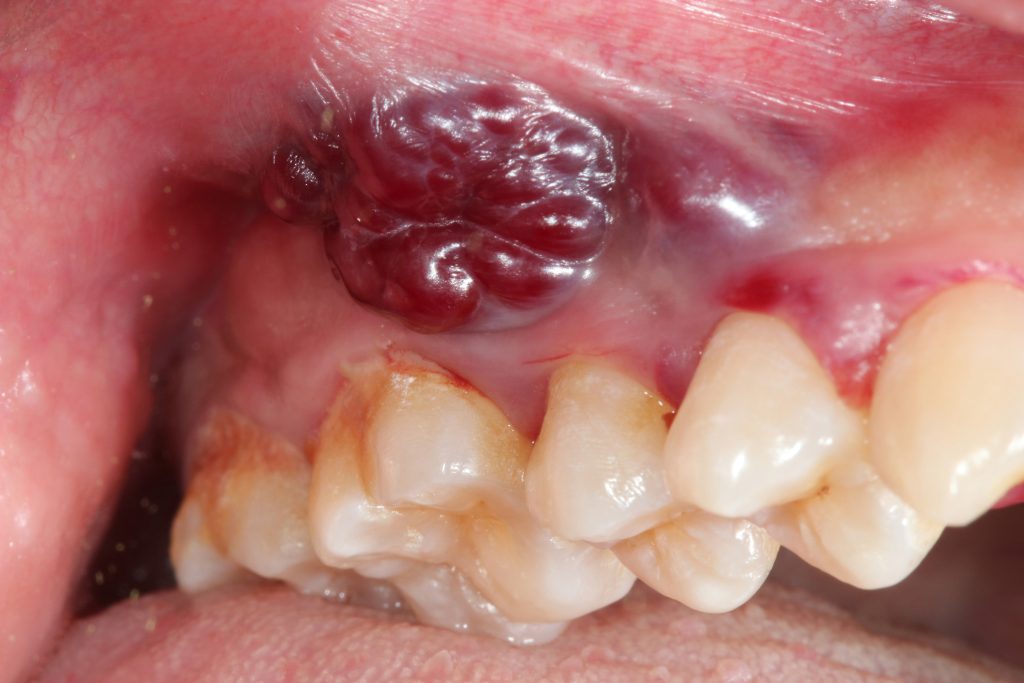

Mundkrebs

Es gibt Würfel, schwer zu schlucken, Gewichtsverlust - nicht nur heiß in